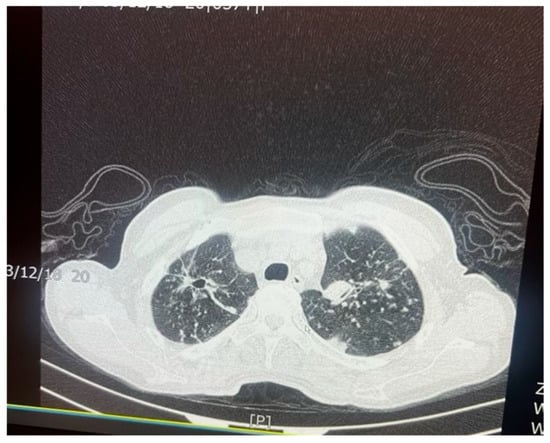

Figure 6. An axial chest CT scan of the same patient in Figure 5, demonstrating advanced nodular and cavitary changes in both lungs, consistent with pulmonary TB. The bilateral upper lobe cavities are clearly visible with associated nodules. The distribution of the lesions, with upper lobe involvement and cavitation, is indicative of reactivation of TB. Additionally, areas of tree-in-bud appearance suggest bronchogenic spread of the infection, which is common in TB patients.

M. tuberculosis can alter the normal lung architecture in cases of both latent and active disease and even cause permanent damage after resolution of the infection. Damage to lung tissue, such as the replacement of tissue with scar tissue, can permanently alter respiratory function, leading to significant morbidity well after the bacterium has been cleared. Figure 5 and Figure 6 illustrate the pattern of damage that points to the reactivation of TB. The cyclical process of tissue injury, immune-mediated inflammation, and healing contributes to fibrosis and calcification, which may lead to both obstructive and restrictive patterns of lung disease. Obstructive dysfunction can result from airway inflammation, loss of elastic recoil, and post-infectious bronchiectasis—the latter characterized by permanent dilation of the bronchi. On the other hand, restrictive changes arise from exaggerated immune responses and chronic inflammation, leading to fibrosis and stiffening of the lung parenchyma. The degree of respiratory mechanic abnormalities (i.e., pulmonary function tests) from M. tuberculosis infection can vary depending on multiple factors such as patient age, geographic location, or the drug resistance of the bacteria [25].